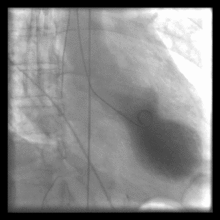

اتساع اپکس به همراه هیپرکینزی قاعدهای در ونتریکولوگرام